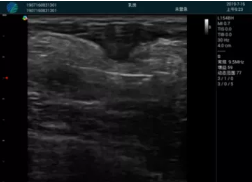

可視化穿刺引導(dǎo)

M20實(shí)時(shí)引導(dǎo):向包塊后方間隙注射利多卡因

清晰顯示腺體內(nèi)低回聲快影,邊界清晰,包膜較光滑

確定進(jìn)針路徑并實(shí)時(shí)監(jiān)測(cè)抽吸針與腫塊位置關(guān)系

抽吸針進(jìn)入腫塊內(nèi)部進(jìn)行旋切

抽吸過程中可見腫塊明顯縮小,并根據(jù)腫塊位置改變針道位置

抽吸旋切后再進(jìn)行超聲復(fù)查,原腫塊區(qū)域未見殘留組織及出血

超聲引導(dǎo)下抽吸旋切取出的腫塊組織